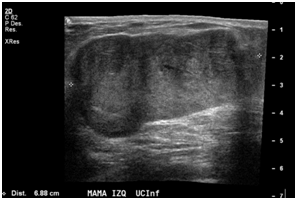

A 47year-old woman with history of a long standing palpable mass on the left breast, which was biopsied on 2006 resulting in hamartoma. She had first degree familiar history of breast cancer with her mother diagnosed younger than 50 \years of age and who later on died of that cause. The patient presented to our office, in June 2016 for progressive growth of her breast tumour. At examination her breasts were fibrous, with a palpable firm and mobile breast mass, not fixed to skin, of 8x6x5cm on the left LIQ, and another large, soft and well defined mass in left LOQ and UOQ of 10x10x5cm, There were no palpable masses in the axilla. On mammography there was a radiolucid well defined breast mass in the left LOQ and UOQ, which was stable in size and shape regarding prior mammogram of twoyears. A new dense, oval and partially defined breast mass was evident in the LIQ (Figure 1). The latter on breast ultrasound corresponded with a hypoechoic and heterogenous nodule with partially defined margins, which measured approximately 7cm. The first lesion was heterogenous and hyperechoic, measured more than 8cm, and was the previously biopsied nodule (Figure 2). She later on underwent a breast MRI that showed a round mass in the LIQ, which was hyperintense in T2, hypointense in T1, had a homogenous enhancement with a plateau curve. In the LOQ there was a well-defined mass, which was heterogenous with fibrous and fatty tissue, and did not enhance with gadolinium (Figure 3). A core biopsy of the two masses was then performed, demonstrating a biphasic fibro-epithelial lesion compatible with a PT at the LIQ, and fibrocystic changes and intraductal hyperplasia without atypia at the LOQ. On August 2016, the patient underwent a partial mastectomy, without incidents, and was sent home on the subsequent day (Figure 4). The definitive biopsy demonstrated that the tumour at the LIQ corresponded to a malignant PT (Figures 5) (Figure 6), and that the LOQ mass was a large breast hamartoma (Figures 7 & Figure 8). Posteriorly, she received 25 radiotherapy fractions, without major adverse effects. She was recently controlled with breast ultrasound and MRI that showed no residual breast lesions.